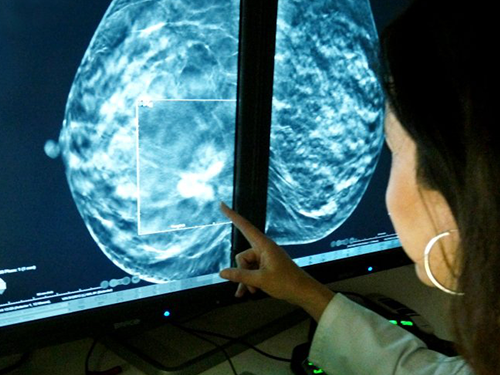

Profesionales formados en campo y académicamente que dan toda su experiencia a nuestros alumnos.